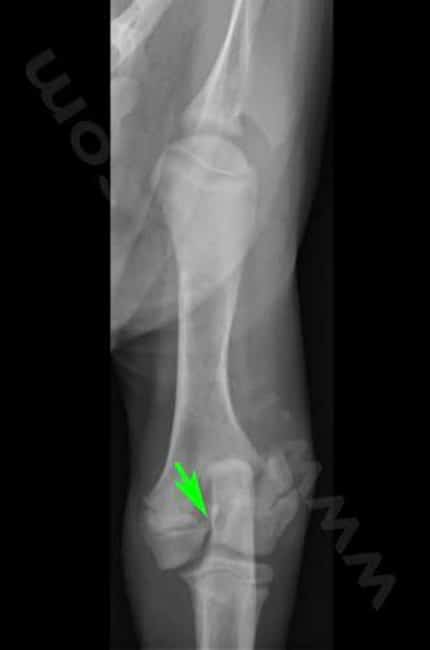

La classification de Salter-Harris des fractures du cartilage de croissance, décrite en médecine humaine donne une indication pronostique : une fracture Salter-Harris de type 1 aura un meilleur pronostic que le type 5. Toutefois, l’âge de l’animal au moment de la fracture et l’implication de l’articulation dans la fracture sont également très importants.

Les risques principaux sont ceux d’une fracture. La fracture est mal localisée et il faudra plus qu’un plâtre pour la réparer. Ces fractures doivent être bien réalignées chirurgicalement et stabilisées par broches, plaque et vis, ou une combinaison. La proximité de l’articulation rends les choses pus complexes.

Le traitement est, comme pour beaucoup de fractures chez le chien, chirurgical. Il faut alors réduire la fracture pour réaligner les abouts osseux et maintenir l’os dans sa conformation naturelle puis la stabiliser avec des implants, le plus souvent des broches qui limitent moins la croissance.

La fracture est réduite, le plus souvent avec des broches et parfois des vis. La quantité de matériel orthopédique est limitée afin de traumatiser le moins possible l’os en croissance. Des radiographies sont réalisées après l’intervention.